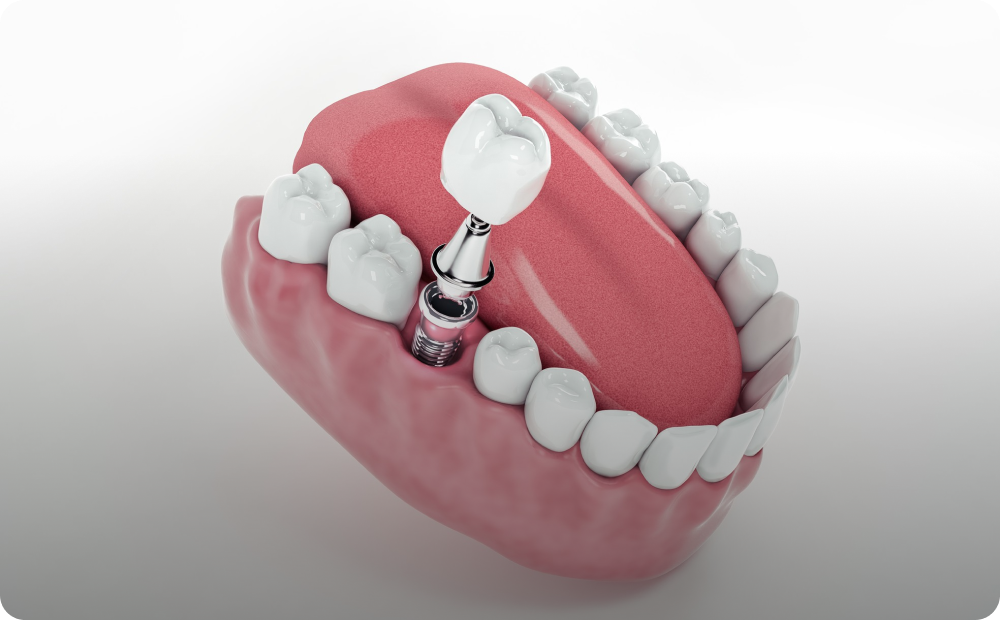

Restauração dental para preservação do dente, recuperando sua forma e função.